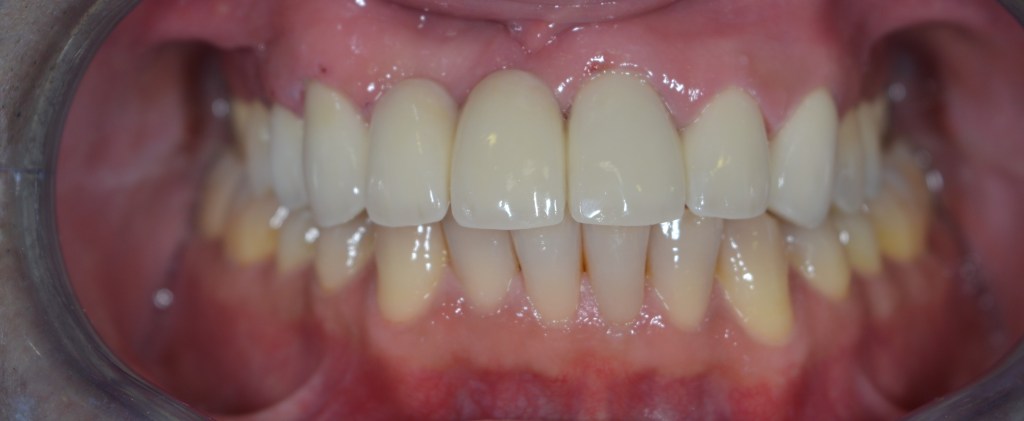

Esztétikai kezelés: felső front műanyag híd cseréje, fogak karakterizálása.

A választott korona típusa: CAD/CAM (komputer vezérelt tervezés/megmunkálás) technológiával készült cirkónium (fémmentes) szóló koronák, illetve híd.

A választott fogszín: D2

A protetikai munka elkészülésének ideje: 5 munkanap.